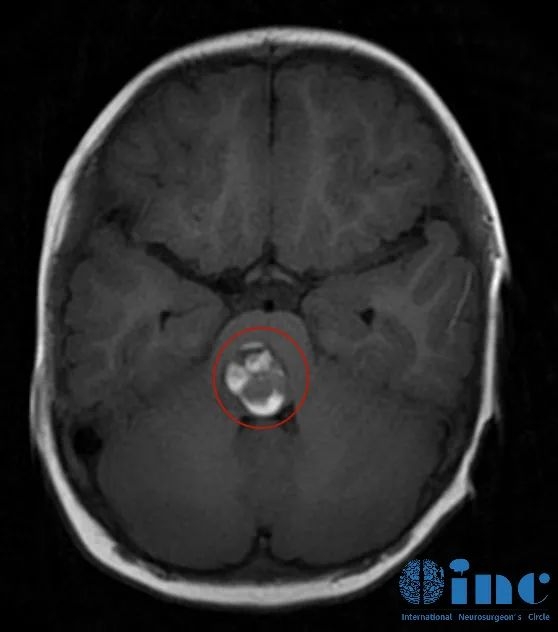

聪聪的脑干海绵状血管瘤病变位置

三年前,聪聪父母带孩子头颅检查发现,原来孩子持续20多天的双眼斜视、不自主扭头、走路不稳等症状是由于脑干海绵状血管瘤破裂出血所致。当地的主治医生表示,脑干出血是神经系统急重症,不及时手术摘除将有生命危险。但由于病变位置在脑干“禁区”,位置很深,在生命中枢的位置,再加上患者又是小孩,手术术中风险及麻醉医生、手术医生、护士等的配合都属于高难度的,稍有不慎就容易波及病变周围神经血管组织造成一些不可逆的后果,如面部或全身瘫痪、视力丧失或终身斜视,重则可能出现呼吸控制需要气管切开等。